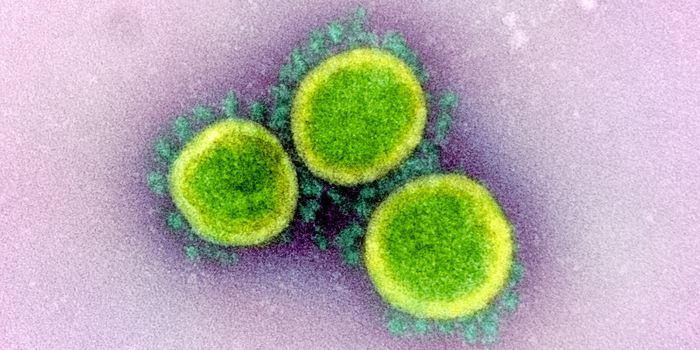

NOV 11, 2021MicrobiologyWhile many people are most familiar with the coronavirus that causes COVID-19, which is called SARS-CoV-2, there are man ...